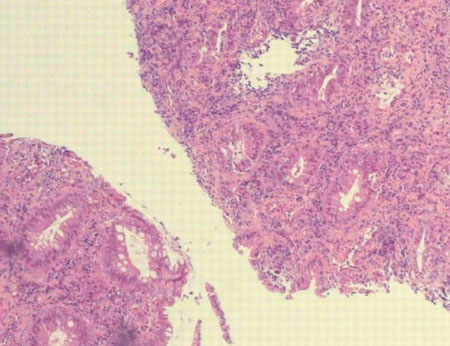

Assessment of proctitis

Rectal mucosa showing non-specific active chronic proctitis in a patient with lymphogranuloma venereum (due to Chlamydia trachomatis)

Laverse E, Jaleel H, Evans D, et al. Sexual history: its importance in averting detrimental misdiagnosis and delayed diagnosis. BMJ Case Reports. 2009; doi: 10.1136/bcr.04.2009.1773